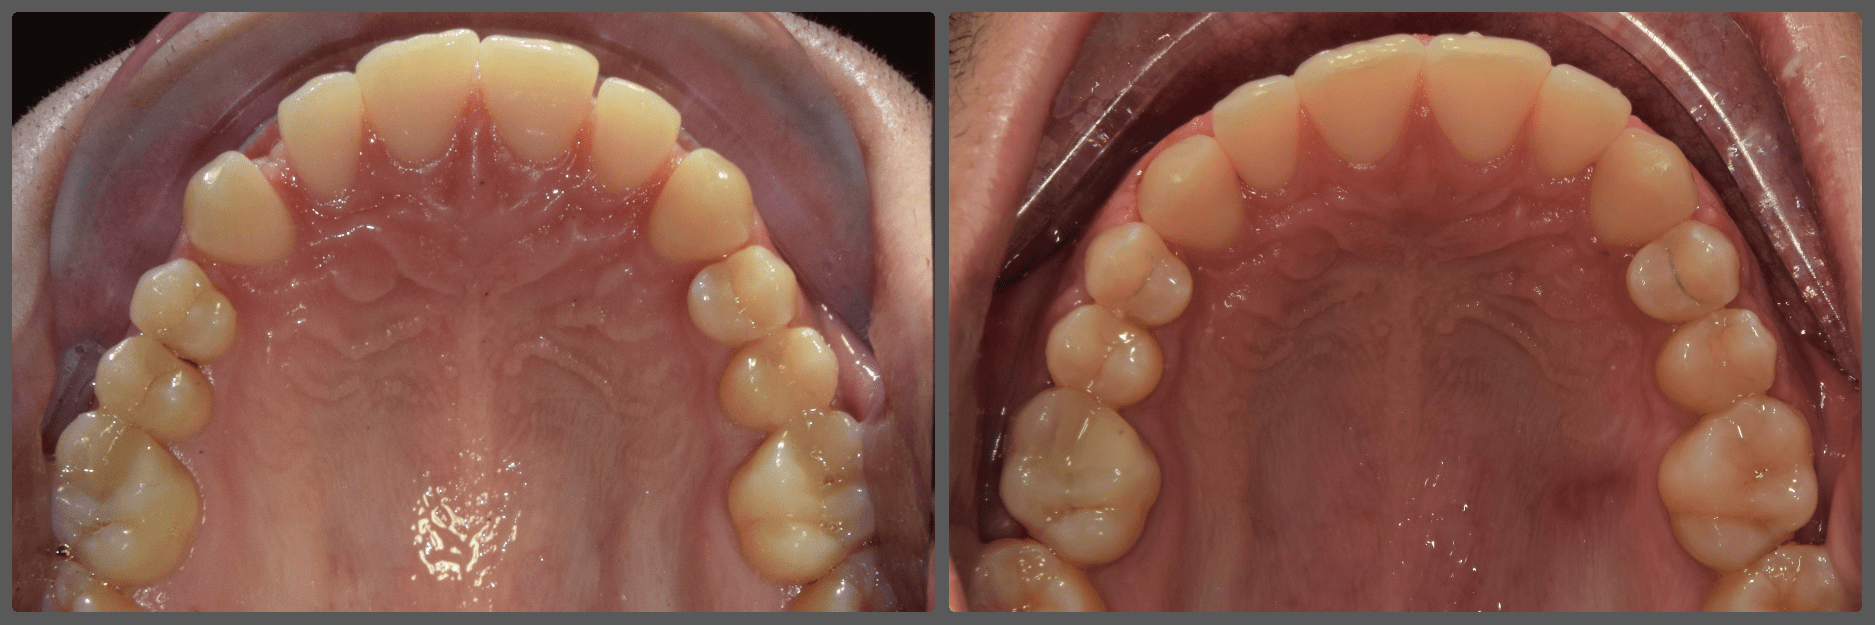

Balázs súlyos alsó torlódása miatt keresett fel magánrendelésemen. A diagnosztikus vizsgálatok során előbbin túl alsó-felső fogívszűkületet, valamint nyitott harapási hajlamot állapítottam meg. Kezelését Pitts21 alsó-felső rögzített fogszabályozó készülékkel kezdtük meg. A nyitott harapási hajlamot a hátsó fogakra helyezett harapásemelővel kontrolláltuk. A torlódott fogaknak tolórugóval és interproximális redukcióval teremtettünk helyet, és intermaxilláris gumihúzással tökéletesítettük a harapást. A fogszabályzó kezelés teljes időtartama alatt Balázs 110%-osan együttműködő volt, ezért 21 hónap alatt sikerült kiemelkedő végeredményt elérnünk.